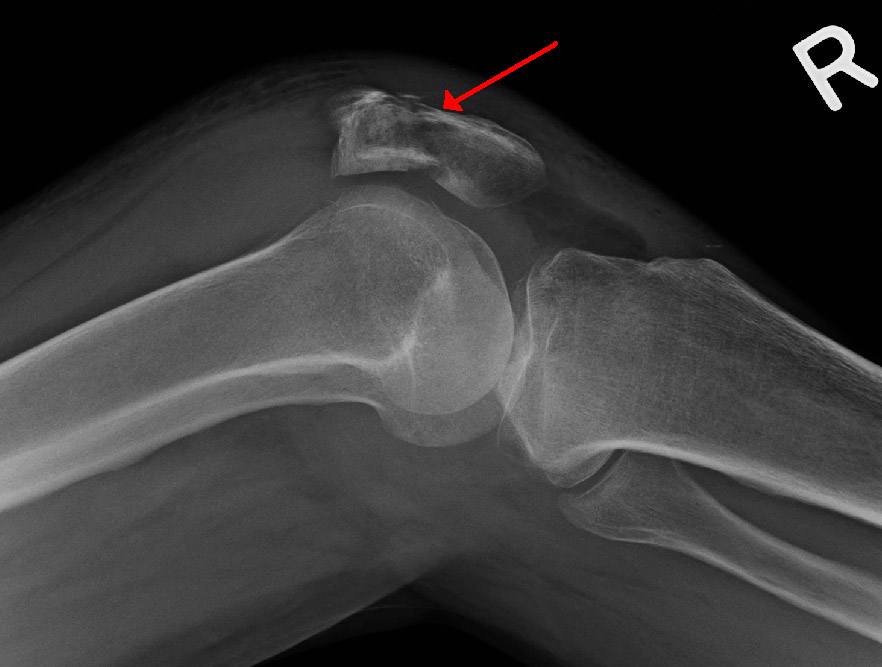

Xương bánh chè có vai trò quan trọng trong việc hỗ trợ và ổn định khớp gối, đặc biệt trong các hoạt động như đi lại và nhảy. Khi xương bánh chè bị tổn thương, sự di chuyển của khớp gối sẽ bị ảnh hưởng, gây ra cảm giác không ổn định và lỏng lẻo.

Tổn thương xương bánh chè thường xảy ra do tai nạn, chấn thương thể thao hoặc ngã, với gãy xương bánh chè là một trong những chấn thương nghiêm trọng nhất. Điều này có thể làm giảm khả năng vận động của người bệnh, gây đau đớn và làm quá trình phục hồi trở nên khó khăn hơn. Việc điều trị tổn thương xương bánh chè đòi hỏi sự can thiệp y tế kịp thời để ổn định khớp gối và phục hồi chức năng di chuyển.

Chấn thương xương bánh chè yêu cầu điều trị kịp thời để đảm bảo khả năng phục hồi chức năng của khớp gối. Trong trường hợp gãy xương bánh chè, việc cố định xương bằng nẹp hoặc phẫu thuật sẽ cần thiết để tạo điều kiện cho quá trình lành xương. Sau đó, người bệnh cần tập vật lý trị liệu gãy xương bánh chè nhằm phục hồi chức năng khớp gối và giảm thiểu các biến chứng, cải thiện sự linh hoạt của khớp và giảm đau.